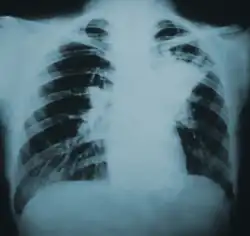

Lung infiltration in blastomycosis.

Blastomycosis manifests as a primary lung infection in about 79% of cases.[8] The onset is relatively slow, and symptoms are suggestive of bacterial pneumonia, often leading to initial treatment with antibacterials. Because the symptoms are variable and nonspecific, blastomycosis is often not even considered in differential diagnosis until antibacterial treatment has failed, unless there are known risk factors or skin lesions.[8] The disease may be misdiagnosed as a carcinoma, leading in some cases to surgical removal of the affected tissue.[19] Upper lung lobes are involved somewhat more frequently than lower lobes.[20] If untreated, many cases progress over months to years to become disseminated blastomycosis.

Blastomycosis in the lungs may present a variety of symptoms, or no symptoms at all.[8] If symptoms are present they may range from mild pneumonia resembling a pneumococcal infection to acute respiratory distress syndrome (ARDS).[8] Common symptoms include fever, chills, headache, coughing, difficulty breathing, chest pain, and malaise.[8] Without treatment, cases may progress to chronic pneumonia or ARDS.[8]